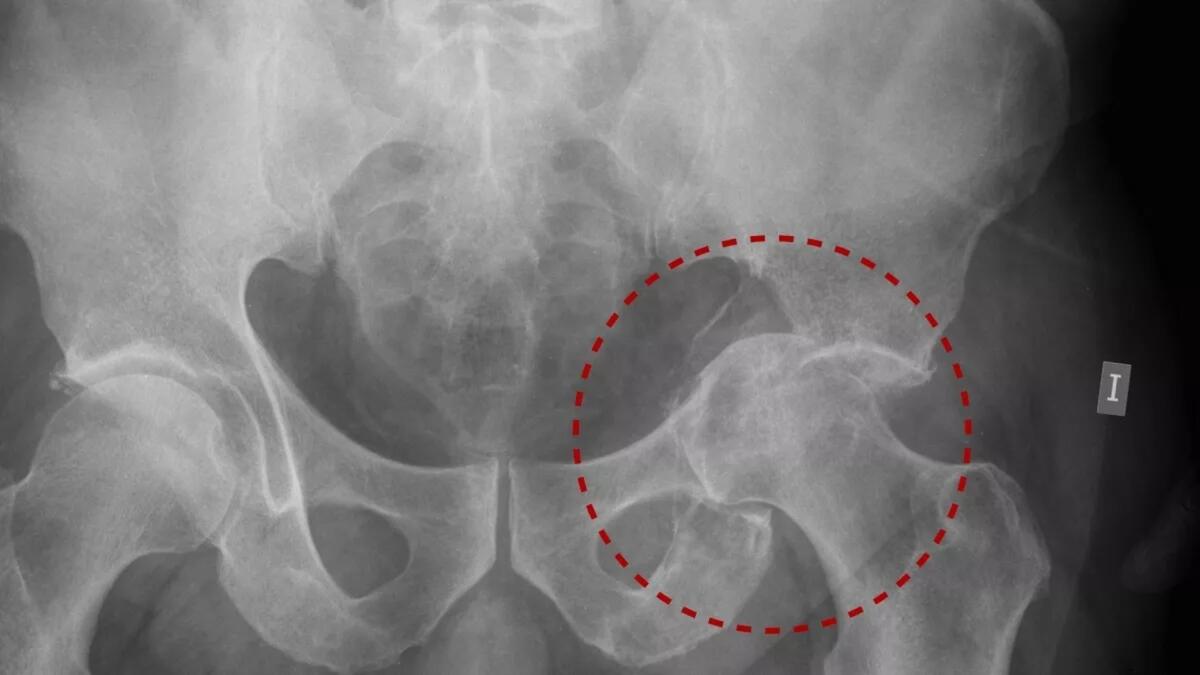

Cuando se presenta una fractura del Acetábulo normalmente implica un mecanismo de muy alta energía, eso quiere decir un golpe o un traumatismo como por ejemplo una rodilla flexionada que se golpea contra el auto en un accidente automovilístico. Este golpe hace que el Fémur se mueva hacia atrás produciendo que se salga de su cavidad, pegue contra los bordes o columnas del Acétabulo y por consiguiente lo fractura. El cartílago de la articulación igualmente recibe impacto, lo cual sumado a la fractura, puede generar en tiempo posterior Artrosis (Osteoartritis).

Para reconstruir la cavidad se utilizan implantes llamados placas y tornillos colocados estratégicamente dependiendo de los patrones de los trazos de la fractura y lograr que vuelva a contener la Cabeza femoral sin que se vuelva a desplazar.